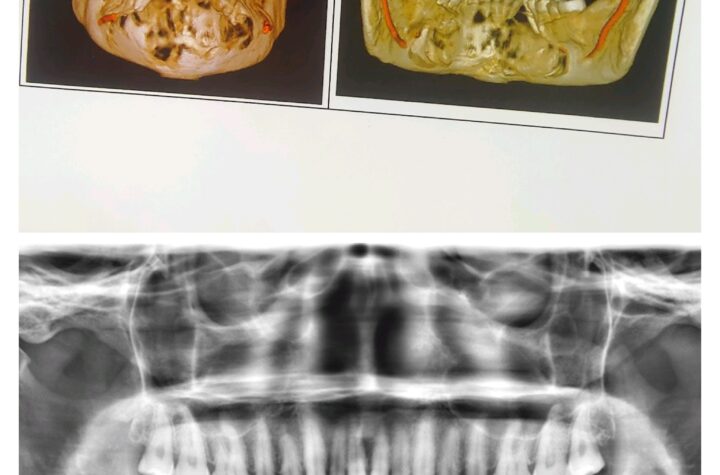

भोपाल: 09 सितंबर 2025 एम्स भोपाल लगातार चिकित्सा शिक्षा और रोगी देखभाल के क्षेत्र में अपनी उल्लेखनीय उपलब्धियों से राष्ट्रीय...

भोपाल: 08 सितंबर 2025 एम्स भोपाल चिकित्सा विज्ञान और एकीकृत स्वास्थ्य अनुसंधान के क्षेत्र में लगातार नई ऊँचाइयाँ प्राप्त कर...